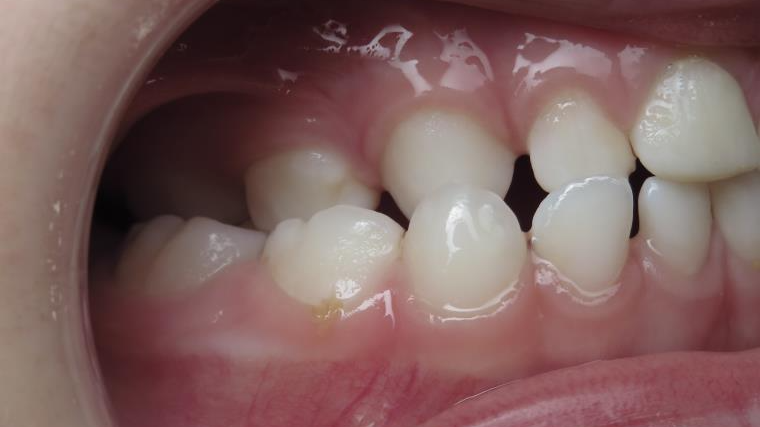

inversion des dents postérieur coté droit

appareillage mobile pendant 13 mois

surveillance de la dentition pendant 16 mois